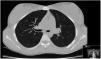

Chest and ribs X-rays were normal. Thoracic CT performed on the same day as the horse kicks, demonstrated two cavities, one in the lower lobe of the right lung with air-fluid level and 70mm diameter (Fig. 1) and other in the medial segment of the middle lobe with 15mm diameter, without broken ribs.